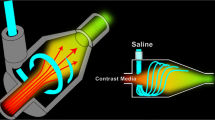

The conventional connecting tube included a T-shaped joint (Fig. 1). The capacity of the conventional connecting tube was 2.2 ml and its length was 60 cm.

The conventional connecting tube (the bi-directional type extension tube for dual injector). The saline inflow opening (red arrow) and the contrast material inflow opening (black arrow). The conventional connecting tube included a T-shaped joint. Both contrast agent injection and saline solution flushing can be handled with one tube

The new connecting tube includes a chamber for generating a spiral flow (Fig. 2a). The spiral flow-generating chamber has a curved inner surface, which is a circumferential inner surface forming a columnar space. The saline inflow opening extends in the tangential direction of the circumference of the curved inner surface (Fig. 2b). The capacity of the new connecting tube was 3.3 ml and its length was 57 cm. In clinical study, the connecting tube was connected to the extension tube (the capacity was 1.0 ml).

The new connecting tube. a The saline inflow opening (red arrow) is formed on an end surface in front of the spiral flow-generating chamber (yellow arrow), and the contrast material inflow opening (black arrow) is formed on a side surface of the spiral flow-generating chamber. b The spiral flow-generating chamber (yellow arrow) has a curved inner surface, which is a circumferential inner surface forming a columnar space. The saline inflow opening (red arrow) extends in the tangential direction of the circumference of the curved inner surface. This causes the generation of a spiral flow of the saline

Movie 1 (Electronic Supplementary Material) was an image obtained by actually imaging the pushed state of the contrast agent using the new connecting tube. The portion appearing black in Movie 1 was the flow of the contrast agent. As understood from Movie 1, the new connecting tube was able to generate the spiral flow.

An image obtained by actually imaging the pushed state of the contrast agent using the new connecting tube. A black ink was mixed to the contrast agent. The saline flow rate was 4 ml/s. The pushed state was imaged by 500 frames per second using a high-speed camera. The portion appearing black in Movie 1 was the flow of the contrast agent. As understood from Movie 1, the new connecting tube was able to generate the spiral flow (MPG 2948 kb)